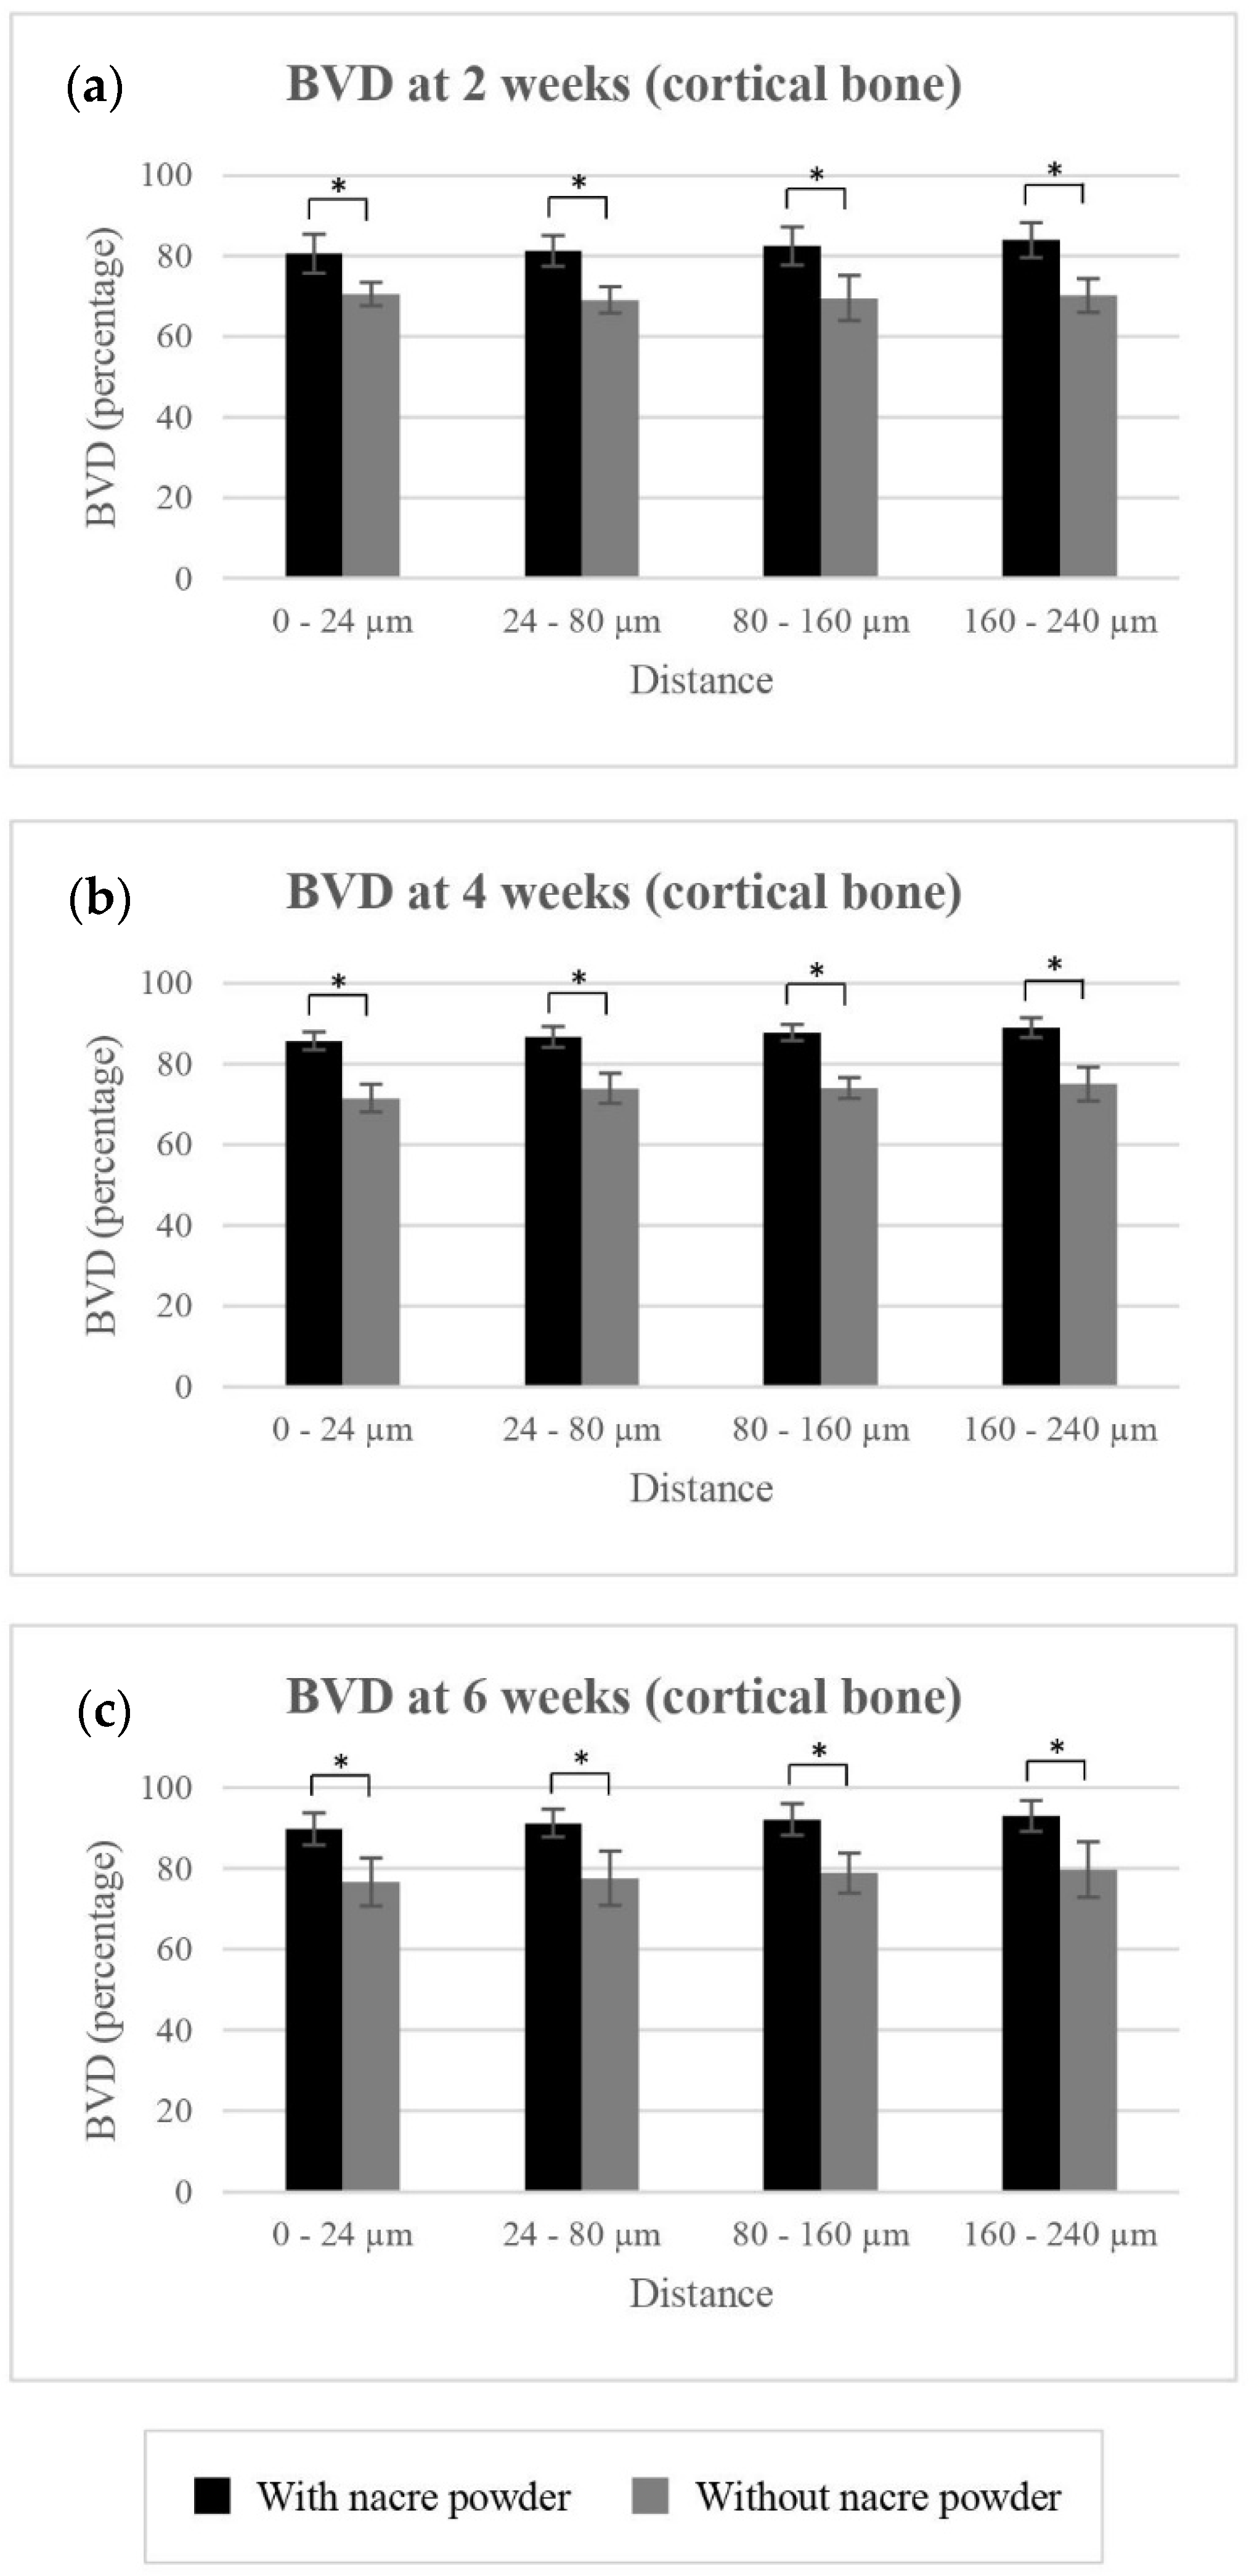

2.2.2. Bone Volume Density (BVD)

BVD of Cortical Bone

| Treatment | |||||||

|---|---|---|---|---|---|---|---|

| Without Nacre Powder (Controls) | With Nacre Powder | ||||||

| Time Points | 2 Weeks | 4 Weeks | 6 Weeks | 2 Weeks | 4 Weeks | 6 Weeks | |

| BVD (%): cortical bone | |||||||

| 0 to 24 µm | 70.52 ± 2.91 | 71.45 ± 3.42 | 76.62 ± 5.97 | 80.61 ± 4.78 | 85.62 ± 2.18 | 89.79 ± 3.94 | |

| 24 to 80 µm | 69.09 ± 3.24 | 73.88 ± 3.77 | 77.62 ± 6.71 | 81.27 ± 3.75 | 86.68 ± 2.63 | 91.21 ± 3.39 | |

| 80 to 160 µm | 69.56 ± 5.64 | 74.01 ± 2.60 | 78.92 ± 4.95 | 82.49 ± 4.75 | 87.78 ± 1.97 | 92.14 ± 3.92 | |

| 160 to 240 µm | 70.22 ± 4.22 | 75.05 ± 4.19 | 79.71 ± 6.85 | 83.96 ± 4.36 | 88.99 ± 2.41 | 93.01 ± 3.77 | |